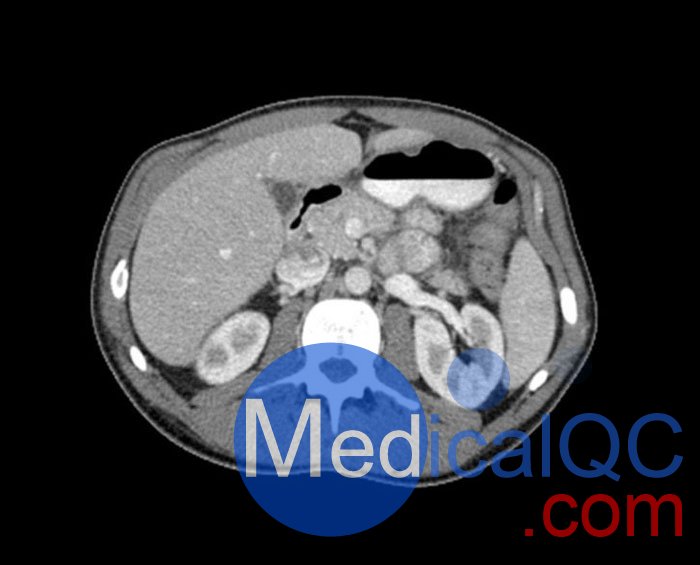

WEK57-01門靜脈期軀干模體,WEK57-01軀干模型模擬了門靜脈期的造影劑增強(qiáng)胸部、腹部和骨盆。它覆蓋了會陰的第二胸椎。

右側(cè)有髂淋巴結(jié)腫塊。

該模型可用于 CT(包括 CBCT)以評估和優(yōu)化成像性能和后處理應(yīng)用,包括支持 AI 的應(yīng)用。它也適用于培訓(xùn)目的。

該模型提供了對軟組織和骨組織的詳細(xì)而逼真的模擬。包括肺在內(nèi)的空隙充滿了大約 -160HU的纖維素聚合物復(fù)合材料。

真實模擬脈管系統(tǒng)、骨骼和軟組織,包括肺、心臟、肝臟、膽囊、胰腺、脾臟、腎上腺、腎臟、胃、小腸、結(jié)腸、膀胱和前列腺。

右側(cè)髂外淋巴結(jié)腫塊。

WEK57-01門靜脈期軀干模體,WEK57-01軀干模型成像效果圖: